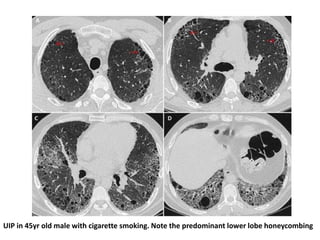

RA-ILD

• RA-ILD manifests most commonly in the UIP-

pattern, and less commonly with NSIP pattern injury

• Patients with RA with a usual interstitial pneumonia (UIP)

pattern on HRCT scan have worsened survival compared

with those with nonspecific interstitial pneumonia (NSIP)

• Drug-induced pneumonitis is an important consideration

in the differential diagnosis of patients with suspected RA-

ILD

UIP in 45yr old male with cigarette smoking. Note the predominant lower lobe honeycombing